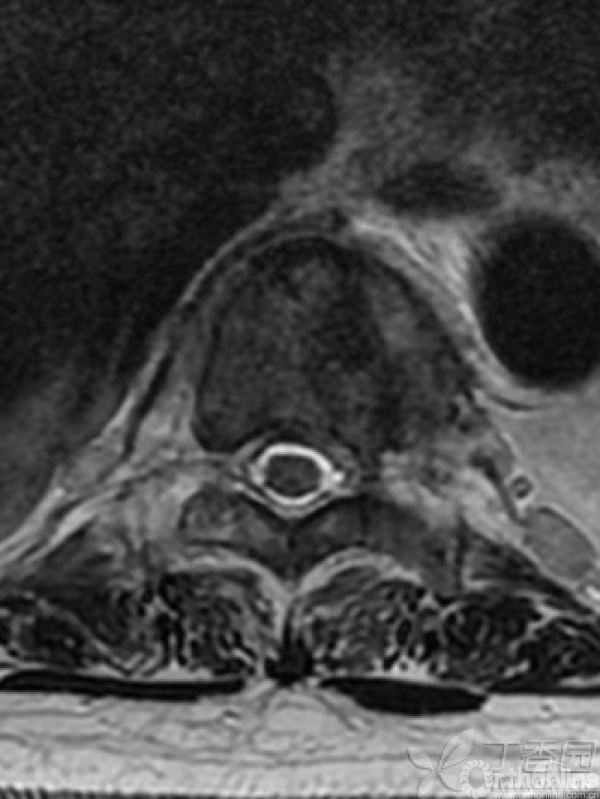

胸椎多椎体病变,如果诊断和治疗?